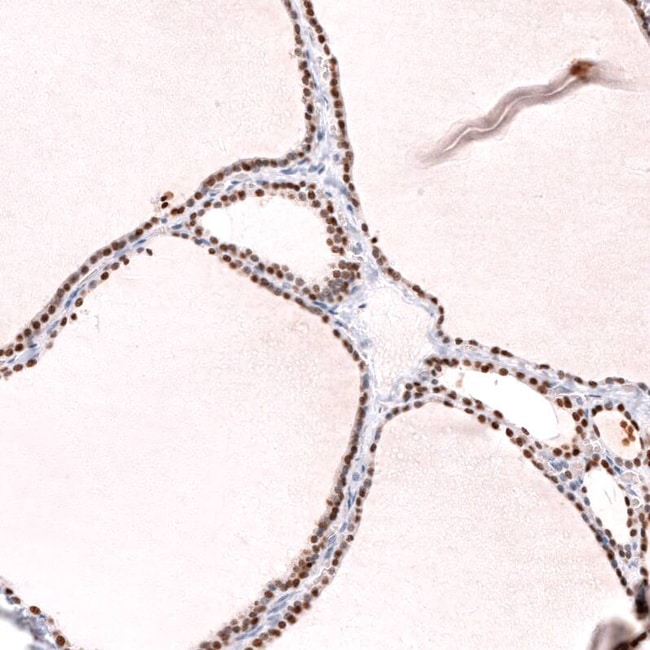

TTF-1/ NKX2-1 Antibody (CL14531) - Azide and BSA Free, Novus Biologicals™

TTF-1 / NKX2-1 Monoclonal antibody specifically detects TTF-1 / NKX2-1 in Human samples. It is validated for Western Blot,Immunohistochemistry (Paraffin),Immunohistochemistry

| Western Blot 1 μg/mL, Immunohistochemistry-Paraffin 1:1000 - 1:2500 | |

| Western Blot, Immunohistochemistry (Paraffin), Immunohistochemistry | |